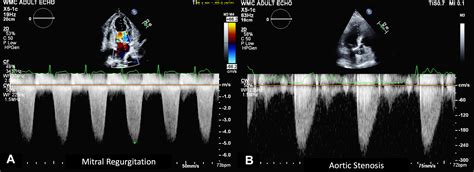

Physicians typically diagnose Severe Aortic Stenosis through a combination of physical examinations and advanced imaging technologies. The most common diagnostic tool is the echocardiogram, which provides a real-time visualization of the valve’s movement and measures the severity of the obstruction.

Transthoracic Echocardiogram (TTE) Valve area, pressure gradient, and left ventricular function.